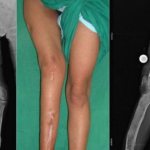

- При поражении более крупной, нежели малоберцовая, кости голень саблеобразно искривляется. Сама она в длину растет значительно медленнее, чем должна. Такое укорочение конечности не может не сказаться на состоянии позвоночного столба.

Поскольку бедренная кость постоянно подвергается большим физическим нагрузкам, деформационные процессы в ее структуре быстро становятся заметны. Обычно они характеризуются искривлением бедра в наружную сторону и укорачиванием конечности. На первых этапах это ведет к изменению походки, далее — к сильной хромоте. Костные искривления провоцируют развитие остеоартроза, что еще больше отягощает ситуацию.

Так как изменения бедренной кости отражаются на работе всего скелета, особенно важно выявить патологию на начальной стадии. Однако, когда бы не была обнаружена фиброзная дисплазия бедренной кости, лечение обязательно будет предусматривать оперативное вмешательство. Стоит сказать, что в большинстве случаев оно проходит удачно и не влечет осложнений.